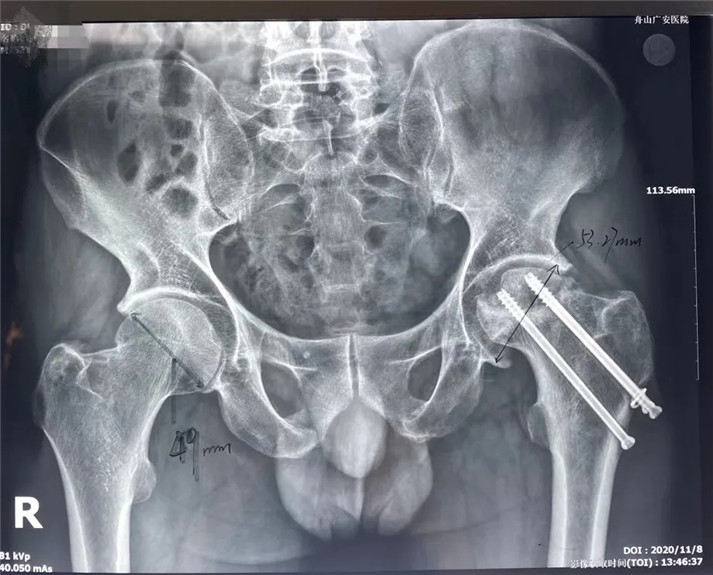

結(jié)合影像學(xué)表現(xiàn)研究后,骨科中心羅軍主任診斷丁先生為左股骨頭壞死,并建議其行全髖關(guān)節(jié)置換手術(shù)。

術(shù)前

考慮到患者的年齡、骨折類型等情況,以及患者的種種擔(dān)憂,為精準(zhǔn)治療、加快愈合、避免關(guān)節(jié)脫位及肢體長(zhǎng)短不等,羅軍主任團(tuán)隊(duì)采用了近期引進(jìn)的AI HIP置換術(shù)前規(guī)劃系統(tǒng)為患者行術(shù)前規(guī)劃。他們將丁先生的術(shù)前CT數(shù)據(jù)導(dǎo)入到系統(tǒng)中,通過自動(dòng)識(shí)別骨盆和股骨建立了計(jì)算機(jī)數(shù)字三維模型。AI HIP顯示患者適合使用合適的髖臼杯、股骨柄、標(biāo)準(zhǔn)陶瓷球頭、陶瓷內(nèi)襯,并精準(zhǔn)定位了截骨線,可以有效幫助醫(yī)生在手術(shù)中做到精確截骨。